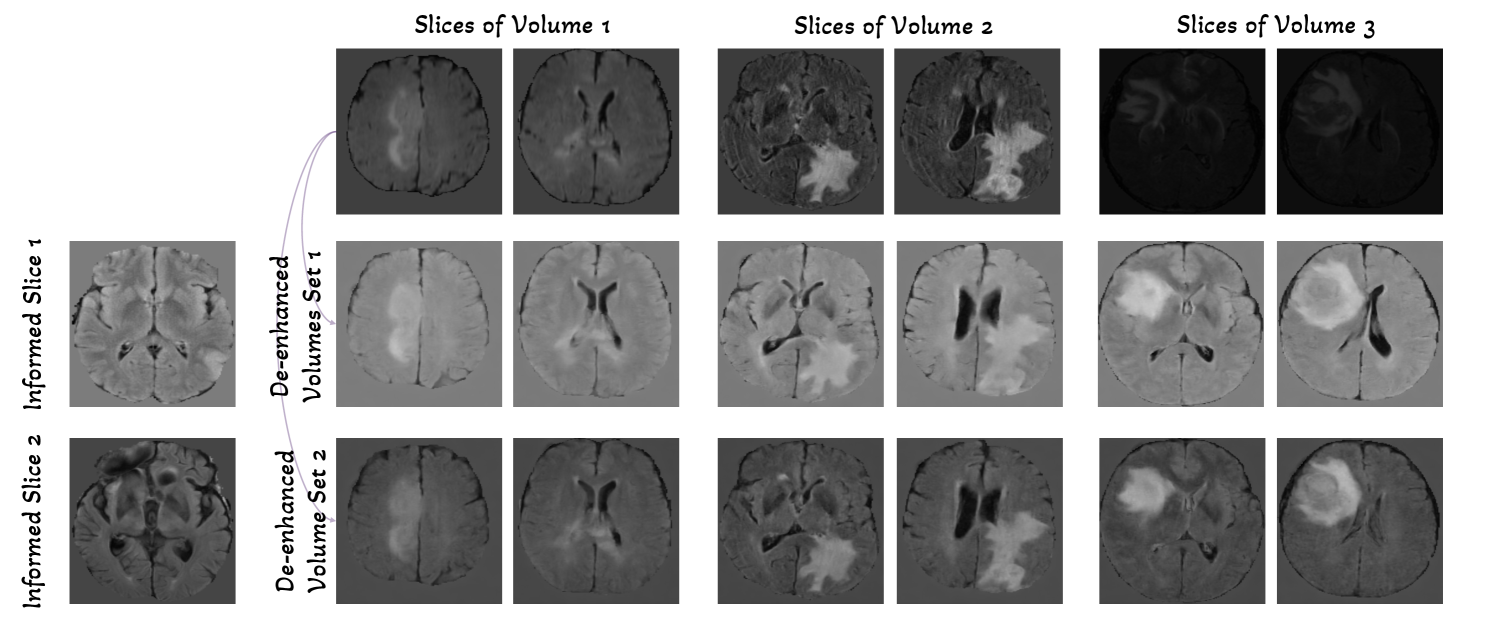

Refer to caption

Figure 4: GEM-3D enables generative de-enhancement. We show three volumes samples on BraTS with the last sample exhibiting poorer visualization quality due to the absence of normalization. Using two choices of informed slices for the initial sampling, GEM-3D generates two types of well-normalized entire volumes through de-enhancement. It is important to note that counterfactual samples are generated for dataset-level normalization, and thus, they are not required to maintain all the anatomical details as observed in the true samples (first row).

GEM-3D Enables De-enhancement. Moreover, we explore the concept of de-enhancement as a reverse normalization process, particularly relevant in medical datasets. Often, these datasets necessitate post-hoc registration and normalization due to variations in imaging protocols, scanner hardware, and patient positioning that can result in inconsistent intensity distributions. We demonstrate that our proposed method, GEM-3D, can be effectively applied to de-enhance the dataset using informed slice control, which acquires the ability for medical harmonization in the dataset level. This technique is similar to other methods [35] that employ GANs to transfer the style of MRI images. To showcase the efficacy of GEM-3D in generating well-normalized volumes, we synthesize volumes with the same informed slice, as illustrated in Fig. 4. This figure displays three volume samples from the BraTS dataset, wherein the last sample exhibits poorer visualization quality due to the lack of normalization. GEM-3D is capable of generating two types of well-normalized volumes through de-enhancement with two choices of informed slices. This de-enhancement approach offers significant contributions to data processing in medical domains, facilitating applications in MRI harmonization for multi-site hospitals.